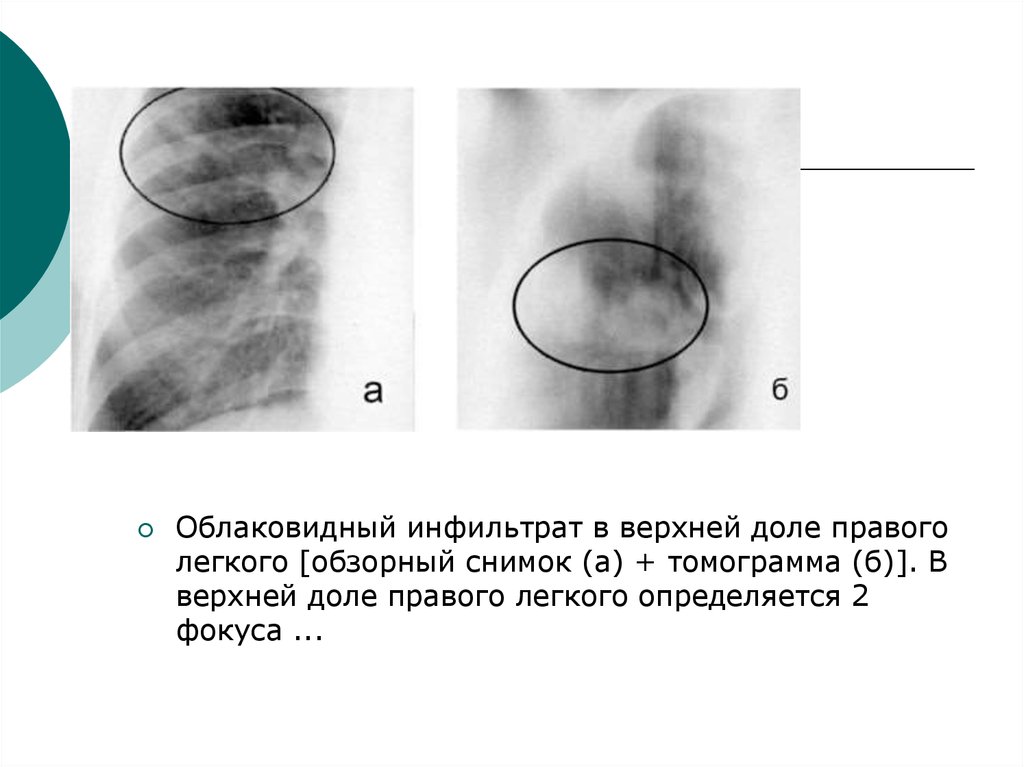

Иллюстрации по теме очагового и инфильтративного туберкулеза